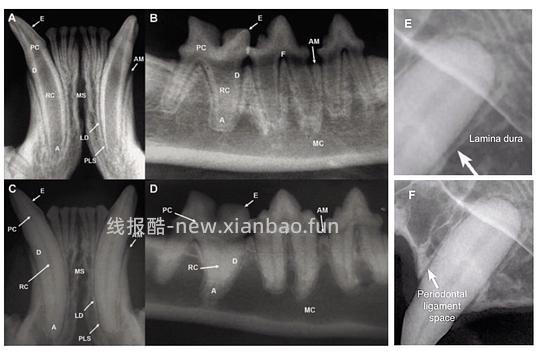

牙齿由四种组织组成,其中,三种是硬组织,分别为牙釉质(Enamel),牙骨质(Cementum)和牙本质(Dentin);一种为软组织,牙髓(Pulp)。牙釉质覆盖牙冠,牙根则由牙骨质包覆,这两种硬组织层在牙齿颈部(Cervical)—即龈下(subgingival)的牙骨质牙釉质交界处(Cemento- enamel junction,CEJ)相接,如图3所示。牙本质是成熟牙齿的主要组成成分,在牙釉质和牙骨质的下层,由约70%的无机物(羟基磷灰石)和30%的有机物(胶原纤维和水)构成。牙髓位于牙齿中心的牙髓腔(Pulp cavity)内,含有结缔组织,神经,淋巴,血管和成牙质细胞等。牙髓腔则由牙冠处较大的髓室(Pulp chamber)和牙根处的细小根管(Root canal)组成。根管在根尖顶端(Apical)分成一些细小的分支形成apical delta与根尖周围牙周组织相连。部分牙齿存在多个牙根,牙根互相分离的位置称为分叉(Furcation)。牙齿结构示意图和x光片见图3,4[1-3]

![【科普】[养猫笔记05-医疗] 猫牙破齿细胞吸收性损伤(FORL)— 猫第二大常见疾病 - 线报酷 【科普】[养猫笔记05-医疗] 猫牙破齿细胞吸收性损伤(FORL)— 猫第二大常见疾病 - 线报酷](https://new.xianbao.fun/plus/api/image.php?imgurl=https://img2.doubanio.com/view/group_topic/m/public/p645118350.jpg)

图4 (a)-(d)不同牙齿x光片(解剖结构:E牙釉质,PC牙髓腔,D牙本质,RC根管,A根尖顶端,AM牙槽骨边缘,LD硬骨板,PLS牙周韧带,F分叉)(E)硬骨板x光图 (F)牙周韧带x光图[1, 3]

牙齿通过牙周组织固定于牙槽窝中。牙周组织由牙龈(Gingival),牙周韧带(periodontal ligament),牙骨质和牙槽骨(Alveolar bone)组成。牙龈附着在牙齿颈部和牙槽骨的大部分冠状区域上。牙槽骨环绕着牙槽窝,最冠状的边缘称为牙槽骨边缘(Alveolar margin)。硬骨板(Lamina dura)覆盖于牙槽骨表面,在影像学上表现为一条白色的阻射线,如图4(E)所示。牙周韧带通过倾斜或水平的胶原纤维束将牙齿连接至牙槽骨上,具有固定牙根和缓解咀嚼压力的作用,x光上可见为一条围绕牙根的黑线(图4(F))[1, 2, 5]。